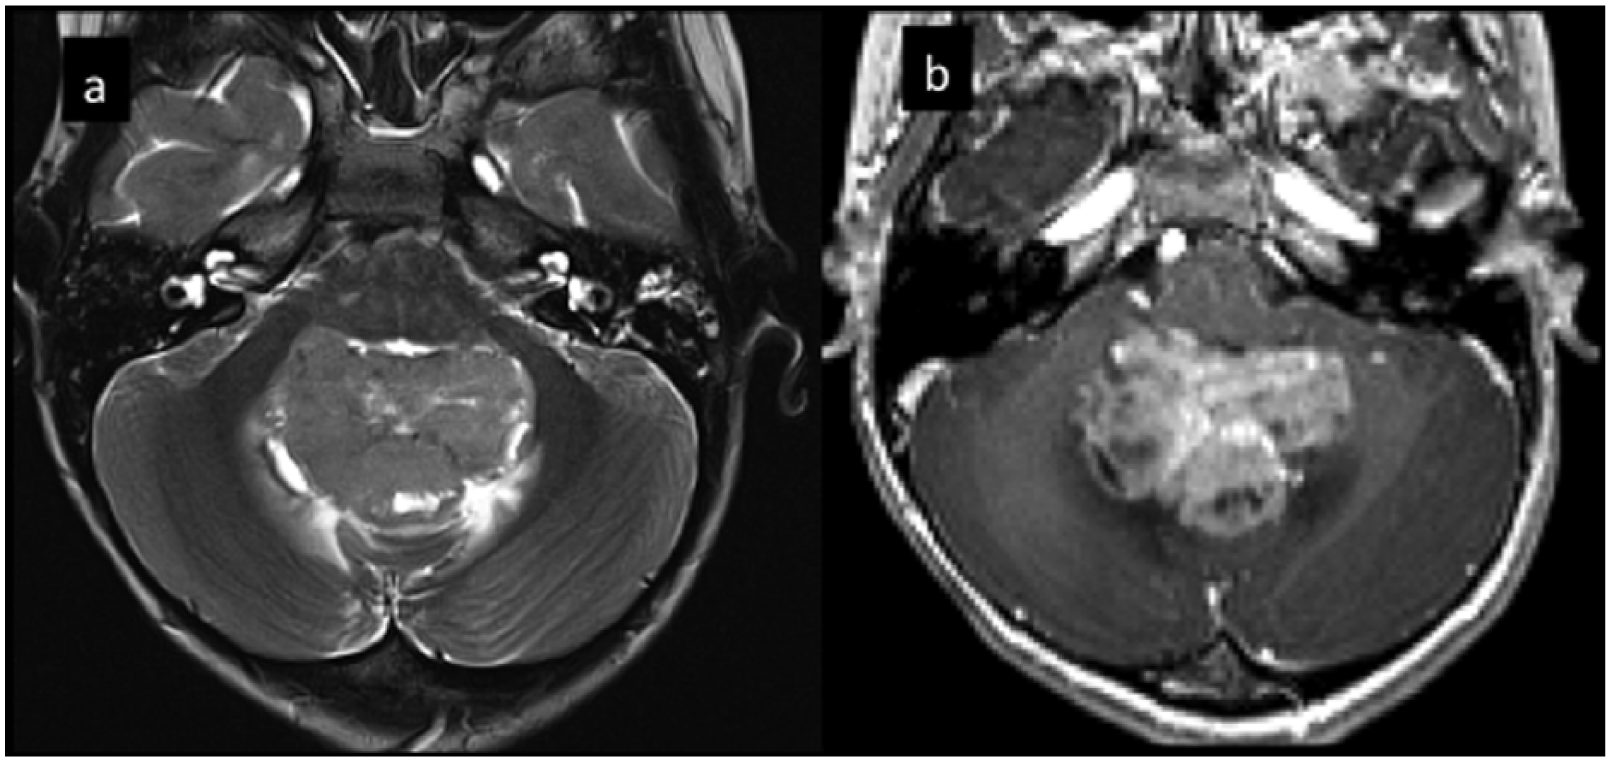

Group 3 accounts for about 25–28% of all medulloblastomas, but these patients have the worst survival and the highest rate of metastatic dissemination (Figure 2).9,34 More common in infants and younger children, Group 3 medulloblastomas are very rare in adults, with a male to female ratio of 2:1. 23 The principal histology is classic or LC/A and the tumor genome is considerably unbalanced, with a large number of broad alterations such as gain of chromosome 7 and iso-chromosome 17q. Associations with neurocutaneous syndromes such as tuberous sclerosis complex have also been described. 35 Group 4 medulloblastomas share many of these alterations (Figure 3). 36 The most common event is the MYC amplification (10–20%), followed by amplification of the OTX2 transcription factor, which accounts for 10% of patients and is mutually exclusive of MYC amplification.37–39

Example of Group 3 medulloblastoma. Five-year-old girl. Axial T2w(a) magnetic resonance images show an intraventricular mass in the fourth ventricle. Axial T1w postcontrast (b) image shows intense contrast enhancement and presence of cystic components.

Example of desmoplastic Group 4 medulloblastoma. Four-year-old girl. Axial T2w(a) magnetic resonance images show an intraventricular mass in the fourth ventricle. Axial T1w postcontrast (b) images show associated homogeneous contrast enhancement.